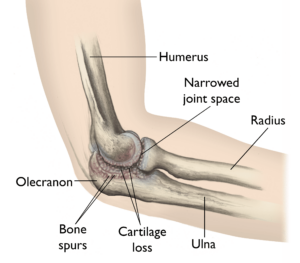

Loose bodies can be caused by old injuries or osteoarthritis in the elbow joint. The most common symptoms are pain and locking. If conservative treatment fails, the condition can be treated surgically by removing any loose bodies.